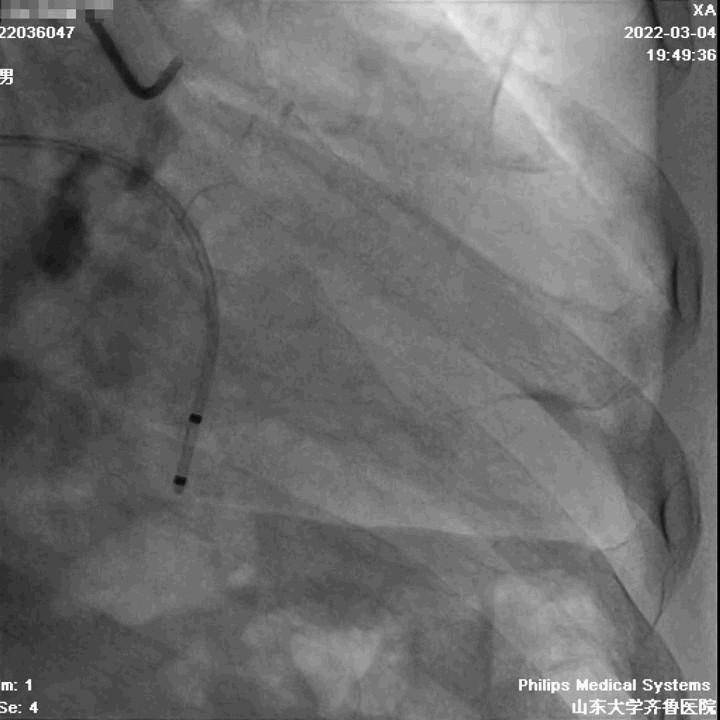

手术过程

第二例病人同样为高难度病例,Type1型L-R融合二叶瓣,钙化积分1300,瓣叶增厚、轻度钙化,钙化分布于瓣叶及左右瓣叶融合脊。

瓣环周长87.4mm,平均径27.1mm。LVOT周长90.5mm,平均径28.5mm。

瓣上4mm/6mm,预估可推开空间周长81.8mm/75.8mm。

在陈院长指导下,李传保主任团队顺利迅速完成了手术,目前病人恢复良好,均已出院。